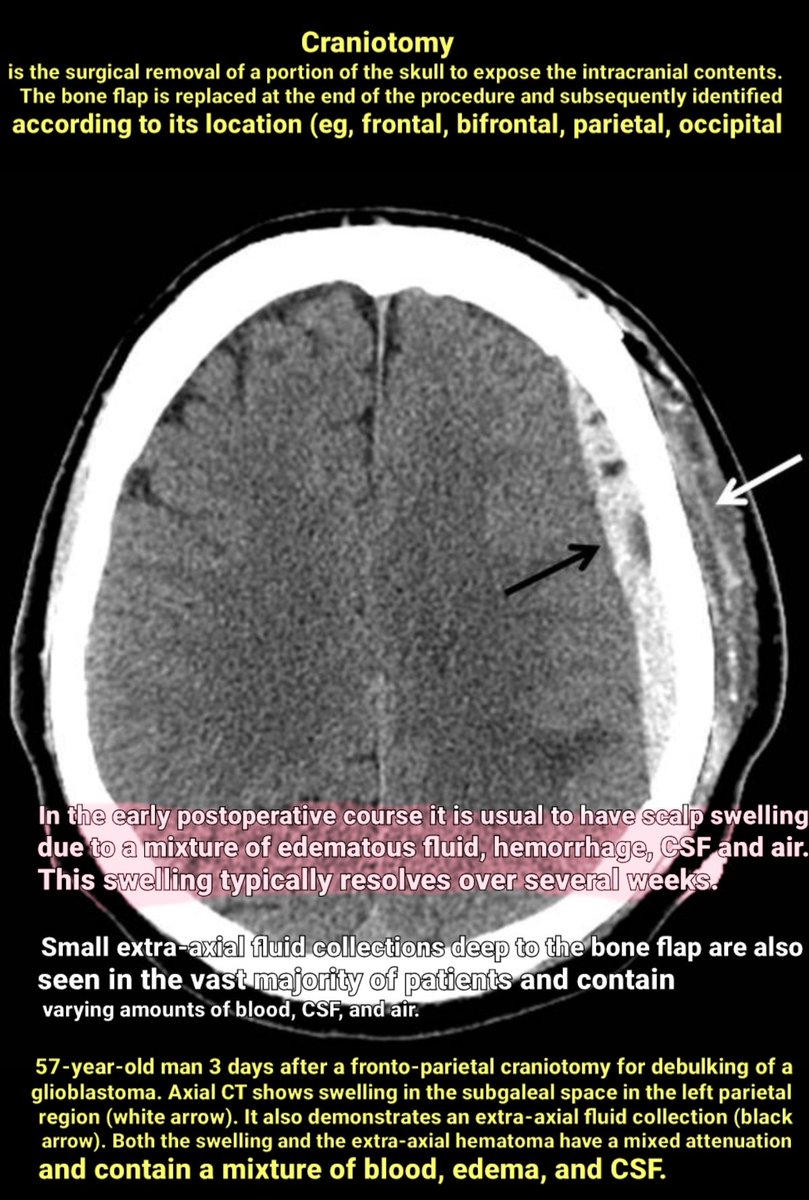

Craniotomy is the surgical removal of a portion of the skull to expose the intracranial contents. The bone flap is replaced at the end of the procedure and subsequently identified according to its location (eg, frontal, bifrontal, parietal, occipital).

Two additional examples👇👇👇